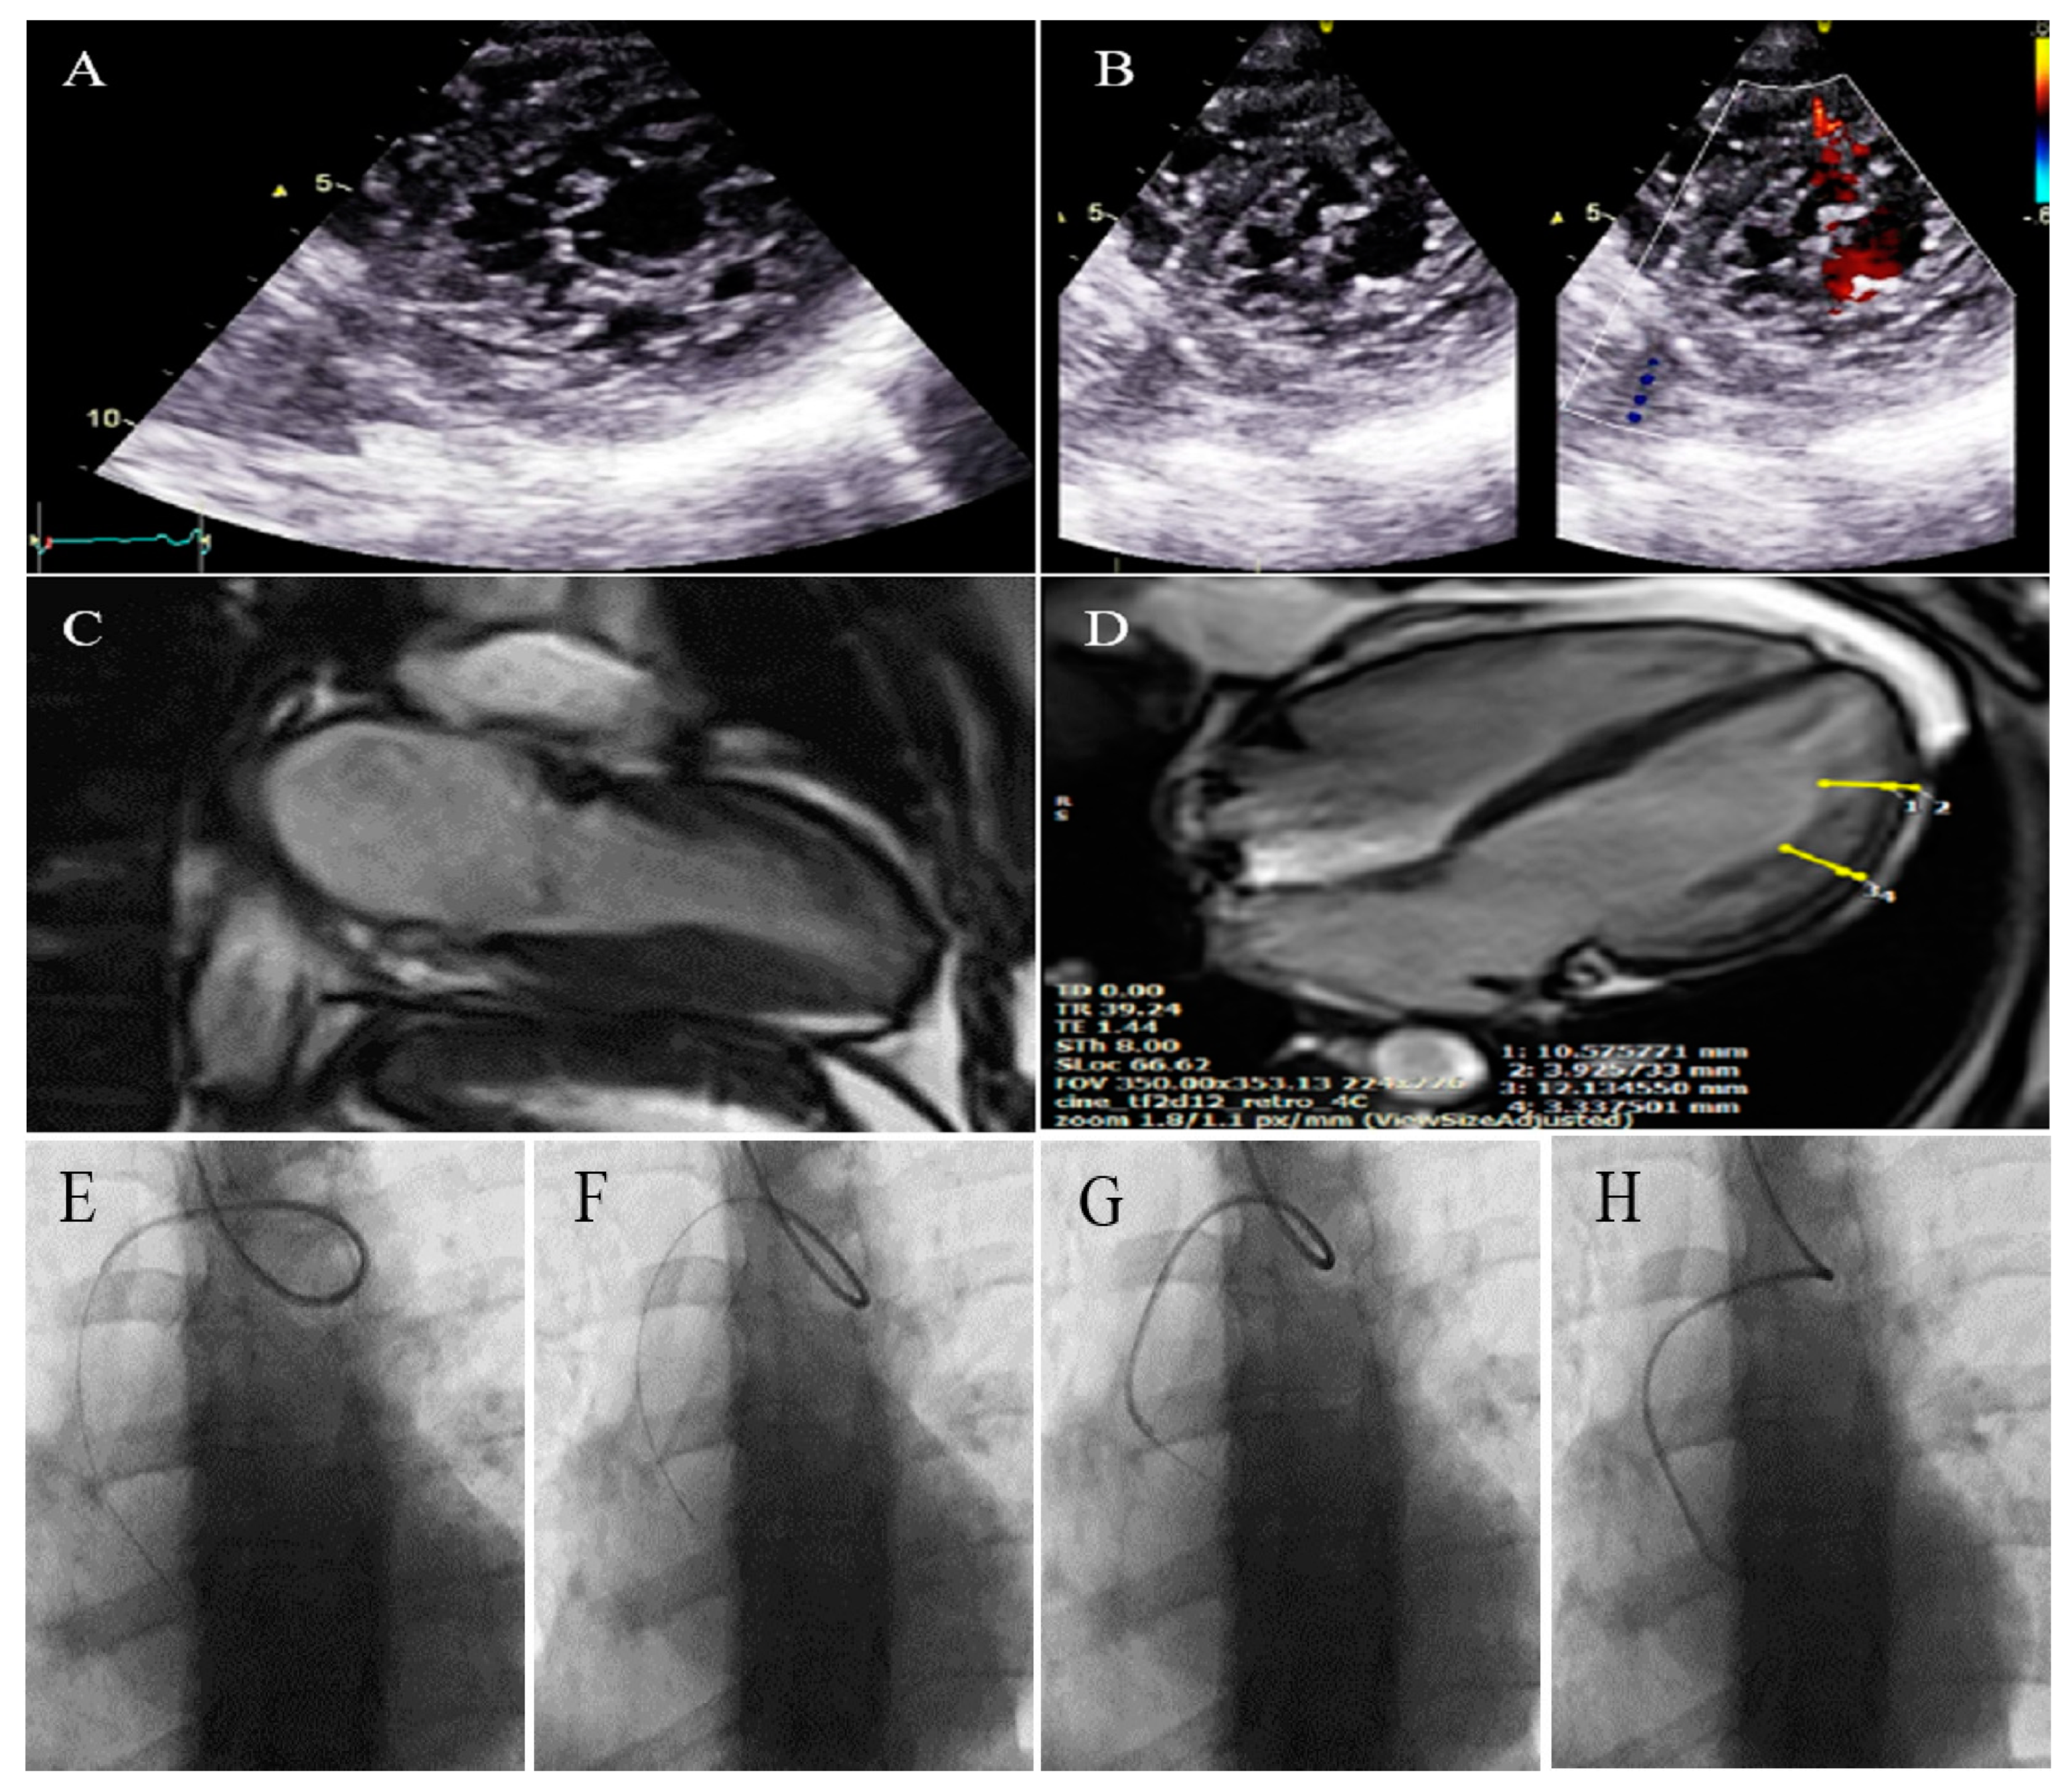

2.1. Case #1. NCLV and Coarctation of the Aorta

A 47-year-old gentleman who worked in the military service for 15 years was referred to our clinic with a complaint of easy fatigability and mild hypertension since 2 years ago. He was followed up with by another colleague who had the impression of mild LV systolic dysfunction and subaortic web. He received 5 mg daily amlodipine; but had mildly raised blood pressure (BP; 140/90 mmHg). When he was referred to our center, there was a discrepancy between the upper and lower extremities’ BP, and cardiac auscultation revealed a loud A2 closure sound. The review of the previously performed CXR showed posterior rib notching at three points. Computed tomography angiography of the aorta confirmed the presence of post-ductal narrowing in the descending aorta. TTE and TEE showed NCLV with mild LV systolic dysfunction (LVEF = 45%) and coarctation of the aorta with a 28 mmHg rest gradient across the coarctation site. CMR confirmed the diagnosis of NCLV (Figure 1). No other associated pathology was noted. A genetic study showed mutations in the MYH7 and MYBPC3 genes; the genetic and echocardiographic results of his siblings (one sister and two brothers) were normal. The patient was recommended to use carvedilol 6.25 mg (three times a day) and spironolactone 25 mg daily. At 1-year follow-up, the patient’s complaints had reduced and the BP was stable.

Figure 1.

The imaging results of case #1. (A); Left ventricular apical short-axis view illustrating hypertrabeculated apical portions in addition to deep intertrabecular recesses, (B); Color Doppler echocardiography, showing evidence of direct blood flow from the ventricular cavity into deep intertrabecular recesses (C); Speckle tracking echocardiographic findings, compatible with myocardial performance impairment plus relative apical sparing; GLS = −10.4%. (D); Prominent trabecular network in the apical lateral segments, (E–H); Thoracic CT angiography, showing narrowing of descending aorta, distal to left subclavian artery in different projections.